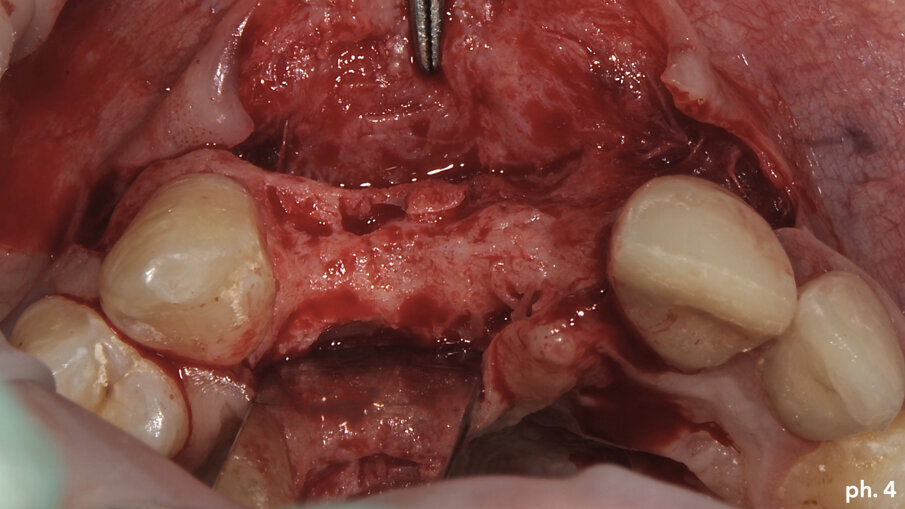

Il paziente, maschio caucasico di 28 anni, si presenta alla nostra osservazione in seguito a un incidente che ha provocato l’avulsione traumatica degli elementi 1.1 e 1.2 con conseguente riduzione dei volumi ossei della zona che, oramai, risulta parzialmente edentula. Sono inoltre presenti in corrispondenza degli elementi 2.1 e 2.2, anch’essi coinvolti nel trauma, due elementi provvisori in resina. La richiesta del paziente è quella di riabilitare la zona edentula con impianti e finalizzazione protesica da 1.2 a 2.2 con corone singole in ceramica1, 2. Dall’esame clinico si evidenzia una carenza di tessuto osseo sia in senso verticale (Fig. 1) che in senso orizzontale (Fig. 2). Si è deciso quindi che l’opzione terapeutica migliore per ottenere una buona rigenerazione ossea di tipo combinato, fosse quella di utilizzare una griglia in titanio customizzata3 in combinazione con un mix di osso bovino deproteinizzato (Geistlich Bio-Oss) e chips ossei prelevati nella zona operata tramite l’utilizzo di un un safe-scraper (Meta)4, il tutto ricoperto da uno strato di matrice Mucograft. Il protocollo operativo delle griglie in titanio customizzate Yxoss CBR prevederebbe l’utilizzo di una membrana in collagene come Geistlich Bio-Gide nella ricopertura della stessa. Personalmente in alcuni casi da me trattati ho deciso di sostituire la membrana in collagene con la matrice, sempre in collagene di origine suina ma in questo caso ricostituito, soprattutto nei settori estetici laddove è richiesta una maggiore quantità di tessuto cheratinizzato al fine di ottenere un risultato estetico migliore. Una volta esposto quindi il tessuto osseo (Figg. 3, 4), si è provveduto ad effettuare una serie di perforazioni a livello della corticale ossea al fine di favorire un regolare sanguinamento (Fig. 5): questo permetterà ai nostri materiali da rigenerazione di usufruire di una maggiore quantità di fattori di crescita, proteine morfogenetiche, ed ottenere quindi una loro migliore integrazione nel tempo.

Una volta riempita la griglia con il mix di osso eterologo e autologo, la stessa è stata posizionata a livello del difetto e stabilizzata tramite l’utilizzo di viti di fissazione autofilettanti (Figg. 6, 7). Il grado di stabilità di queste griglie in titanio customizzate CAD/CAM è assolutamente elevatissimo, così come il loro grado di precisione. Stabilizzata in maniera perfetta la griglia, la stessa è stata ricoperta con uno strato di Geistlich Mucograft in modo da permettere la miglior maturazione possibile dei tessuti molli in fase di guarigione (Fig. 8). Al momento della chiusura del lembo è stato necessario effettuare un’incisione per il rilascio del periostio per ottenere una guarigione per prima intenzione, aspetto fondamentale affinché la maturazione di tali presìdi risulti perfetta. Il tempo di guarigione suggerito dalla letteratura prima della rimozione della griglia è di circa otto mesi; personalmente aspetto sempre 12 mesi prima di inserire impianti in una zona di osso rigenerato, e così è stato anche in questa situazione. L’immagine numero 9 rappresenta la guarigione a un anno di distanza e la relativa radiografia di controllo (Fig. 9). L’attesa così prolungata porta a far sì che la fase chirurgica della rimozione delle griglie in titanio sia l’aspetto più complesso di tutto il trattamento. Questo perché le aderenze di tipo fibroso che si creano tra i tessuti molli e la griglia stessa rendono difficile l’asportazione soprattutto a livello palatale e linguale (Fig. 10).